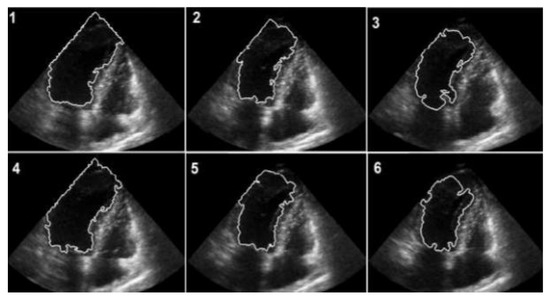

The numerical outcomes of the proposed as well as existing techniques are presented in this section. The input image of echocardiograms is given in Figure 4, and the pre-processed image is given in Figure 5. The FCM based segmentation is accomplished in echo images that is illustrated in Figure 6.

Figure 6.

FCM-based segmented images.